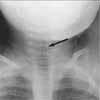

Radiographs of the neck can help confirm the diagnosis of croup and exclude other causes of the croup syndrome. The anteroposterior view may demonstrate subglottic narrowing--the classic "steeple sign" of croup (Figure 1, left). Lateral films may demonstrate an overly distended hypopharynx.

Keep in mind that in approximately 50% of children with croup, the steeple sign is not visible on radiographs (giving a false-negative result). Moreover, subglottic narrowing can be present in children who do not have croup (giving a false-positive result). This suggests that radiographs should be used judiciously in the diagnosis of croup and are best reserved for children with atypical presentations.